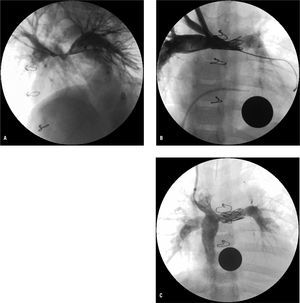

En cuanto a la afección de las arterias pulmonares, se realizaron 10 angioplastias en 7 pacientes (3 casos presentaron restenosis precoz tras una angioplastia inicialmente efectiva). De los 10 niños a los que se había realizado Norwood clásico (fístula Blalock-Taussig a arteria pulmonar derecha), encontramos desconexión de arteria pulmonar izquierda en 2 pacientes y en un tercero, estenosis crítica en su origen. En este último caso se realizó angioplastia con balón a través de la fístula quirúrgica, con buen resultado, pero en pocos meses evolucionó a desconexión de la arteria pulmonar izquierda, por lo que finalmente se le realizó Fontan fenestrado al pulmón derecho; actualmente la paciente permanece con saturación del 85% y en grado funcional I. Otros 3 pacientes con Norwood clásico precisaron, después del estadio II y antes de la realización del Fontan, angioplastia con stent de arterias pulmonares, que se realizó por vía venosa yugular (a través del Glenn) con stents EV3 de 26 mm (n = 1), CP de Numed (n = 1, fig. 2) y Palmaz P188 (n = 1). En uno de ellos se redilató el stent al año de su implantación y en los tres se completó el Fontan con éxito.

Fig. 2. A: angiografía (oblicua anterior izquierda) en paciente de 3 años, con Norwood clásico y Glenn, que desarrolló hipoplasia severa de la zona de confluencia entre ambas arterias pulmonares. B: angiografía anteroposterior tras angioplastia con balón y posterior implantación de stent CP de 22 mm (Numed®). C: angiografía en vena cava inferior tras completar el Fontan, 6 meses después de la redilatación del stent.

En cuanto a la afección de las arterias pulmonares, la técnica modificada de Sano (shunt desde el ventrículo derecho) evitó en nuestros pacientes el problema de la desconexión o hipodesarrollo de la arteria pulmonar izquierda, pero no evitó las estenosis de arterias pulmonares en la zona de inserción del conducto22. La incidencia de estenosis significativa de ramas pulmonares tras la cirugía Norwood (antes del Glenn o Fontan o incluso después de éste) referida en la literatura oscila entre el 40 y el 62%23,24. En nuestra serie observamos especial tendencia a presentar estenosis severas y/o hipodesarrollo en la zona de confluencia entre ambas arterias pulmonares, donde pueden quedar restos de tejido ductal, y que resulta más difícilmente accesible al cirujano por quedar posterior a la neoaorta ascendente, habitualmente dilatada. Otro factor posiblemente implicado en el hipodesarrollo de esta zona es la presencia de doble cava superior, pues tras el Glenn el flujo de cada vena cava superior se dirige a la arteria pulmonar ipsolateral; 2 de los 3 pacientes que precisaron stent en esa zona presentaban doble cava superior. Otra de las peculiaridades de las angioplastias de arterias pulmonares realizadas en pacientes tras los estadios I o II es que presentan elevada incidencia de reestenosis (posiblemente por persistencia de tejido ductal), pero también suele tratarse de pacientes de bajo peso y pequeño tamaño de las arterias pulmonares que no permiten en algunos casos la implantación de stents redilatables. Para el seguimiento de estas estenosis tras la angioplastia, es fundamental la utilización de la RM o angiografía por TC. La implantación de stents de menor tamaño (coronarios o periféricos) y que precisan introductores de menor tamaño podría ser una opción, pero limitan el desarrollo de la arteria y con el crecimiento somático del paciente acaban creando una estenosis. En nuestros pacientes, intentamos utilizar la angioplastia con balón en los pacientes más pequeños (aunque precisaran redilatación por reestenosis a corto o medio plazo), y retrasar la implantación del stent para emplear stents redilatables (Palmaz, Ev3 o CP de Numed) a través de vainas de 10-11 Fr, que se introdujeron sin complicaciones por la vena yugular en niños de hasta 10 kg de peso. Quizá en el futuro el empleo de nuevos stents pediátricos, como los reabsorbibles25 (Biotronik) o redilatables de bajo perfil (growth stent)26, aún en fase de ensayo clínico, podrían facilitar y mejorar el tratamiento de estas lesiones. Por otra parte, la implantación de stents en la zona de la confluencia de las arterias pulmonares puede condicionar la técnica quirúrgica empleada en el estadio III: en 2 de nuestros pacientes con el stent en esta posición el conducto extracardiaco desde vena cava inferior tuvo que ser anastomosado a la arteria pulmonar derecha, frente a la conexión del Glenn (fig. 2B), y el postoperatorio transcurrió sin complicaciones.